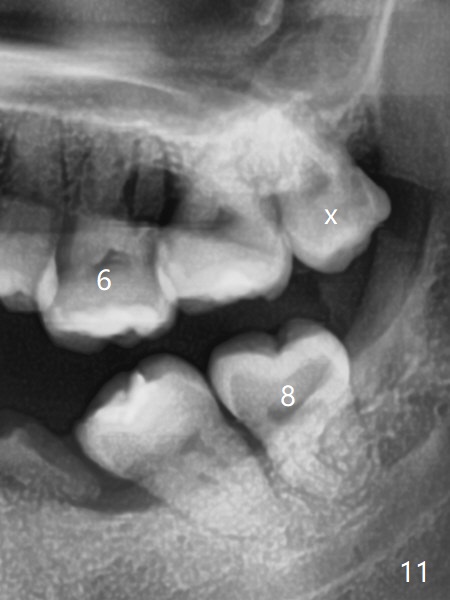

矫正器放置后一个月,正好有充裕时间,匆忙研究全景片(最好CT),好像左上6近中间隙大,近中颊侧,远中腭侧似乎是种植位点(图一:白圆圈),植入越高越宽,不容易伤及邻牙牙根。但是微型植体种植原则是必须种植在角化龈,减少炎症(以前不明白为什么)。当植体在移动牙龈植入时(图二:白箭头),牙龈浮起来,估计非角化牙龈也不能与植体产生紧密结合。取出后,完全可以在6近中颊侧角化龈植入,但是仔细检查发现远中颊侧角化龈更宽,所以在那里扎根(图二:黑箭头),因此腭侧就得选择近中(图三)。微型植体可以即刻使用,power chains常滑脱,压迫牙龈,在这个病例很可能进入远中牙间隙,所以需要在远中边缘嵴加树脂(图四,五:* (1.6x8mm))。第二天远中颊侧植体松动,取出后,插入2x10毫米一段式植体,仍然松动(图六)。CT显示植体下缘穿破牙槽骨(图七,骨质吸收严重与图八近中牙槽骨高度对比)。如果在近中颊侧重新植入微型植体,必须使用6毫米长植体(图九),所以最好在远中颊侧重新植入(图十:红色),缺损区(黑色)植骨。在使用14 niti时,左下7松动,病人同意拔除8,以后后推7,然后6种植(图十一:(左上8已拔除(x))),同时左上6远中植骨,左下8远中牙槽窝放置浸泡PRF液体胶原塞(图十二:1),近中牙槽窝粘性骨粉(2),最后牙槽窝上部PRF膜(3),PGA缝线。可能需要Cytoplast。